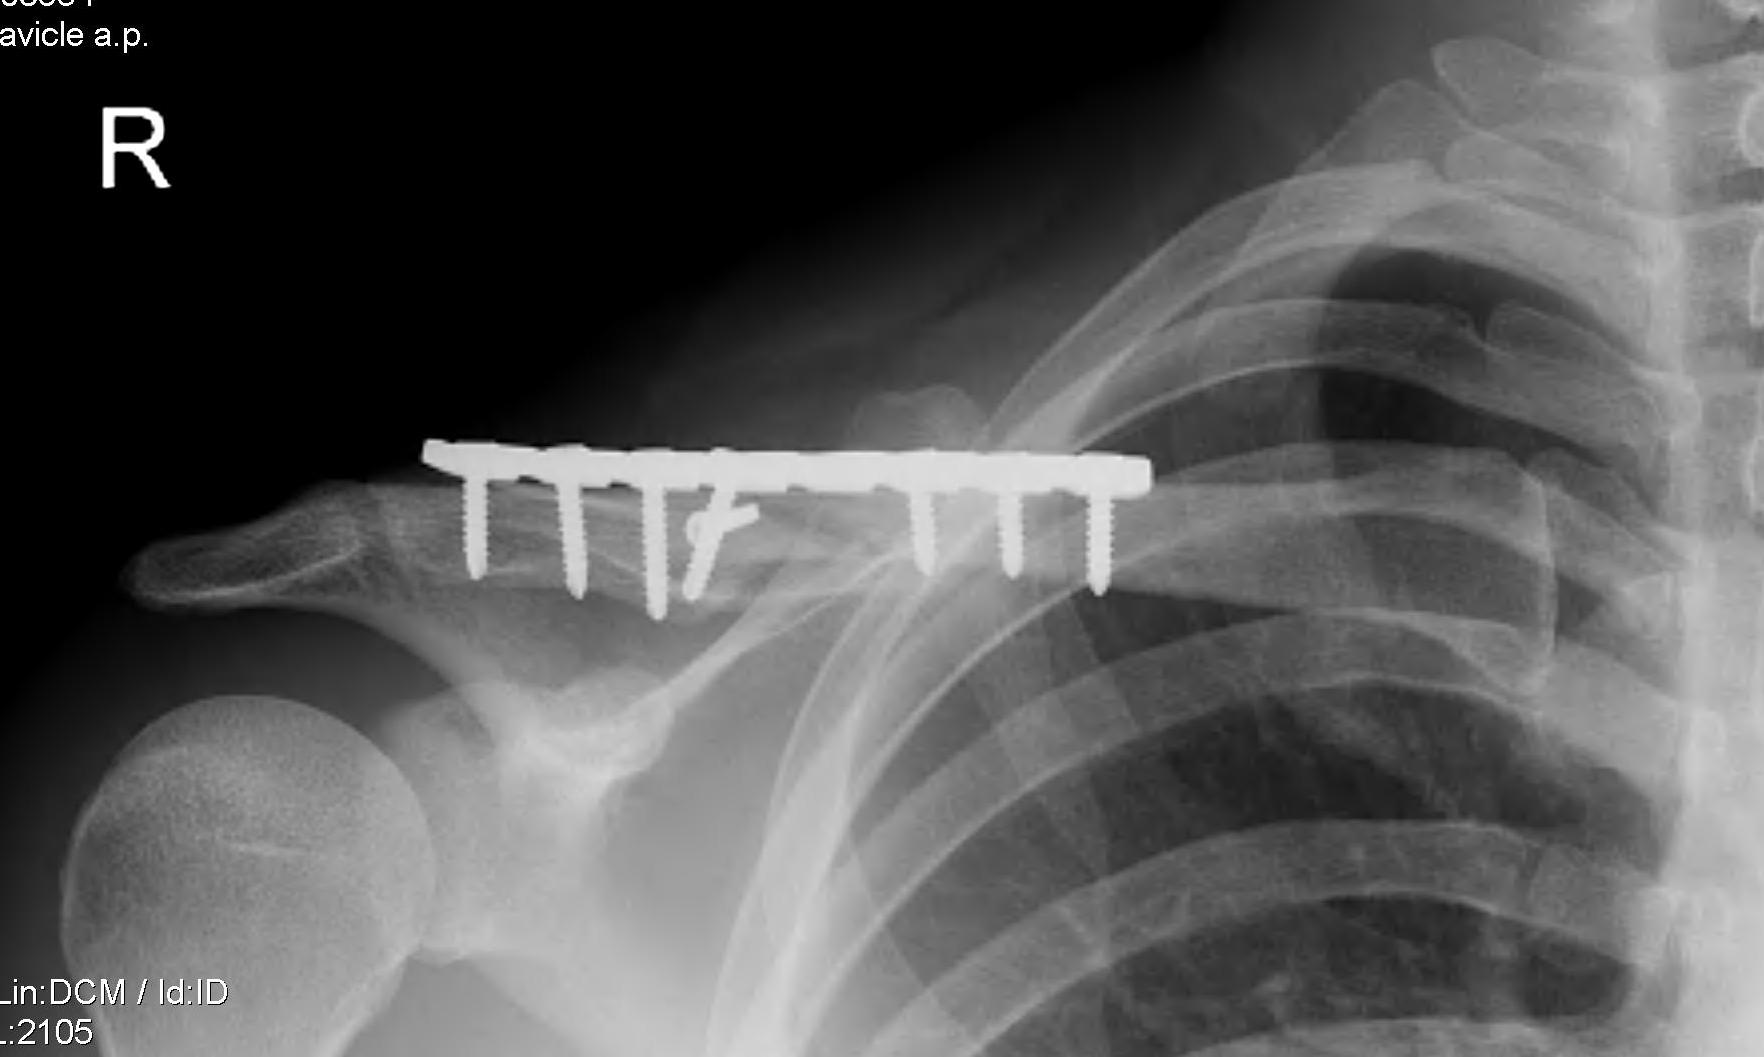

Plate fixation of shorted displaced midshaft clavicle fractures reduces nonunion rates

Operative Management

Plate fixation

Superior versus anteroinferior plates

Nourian et al J Orthop Trauma 2017

- systematic review of superior v anteroinferior plates

- no difference in outcome or union rates

- higher incidence sympomatic hardware with superior plates

Technique

- clean and reduce fracture

- application contoured locking plate

- need 6 cortices each side